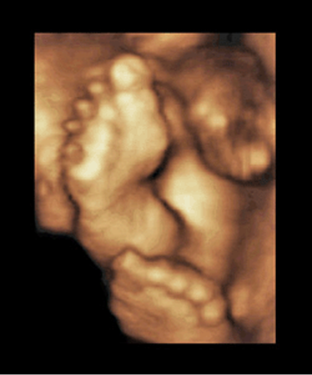

FIGURE 8–26. Three-dimensional sonogram of fetal feet and toes. (Courtesy of Philips Healthcare.)

FIGURE 8–27. Three-dimensional sonogram showing bilateral club feet. (Courtesy of Philips Healthcare.)